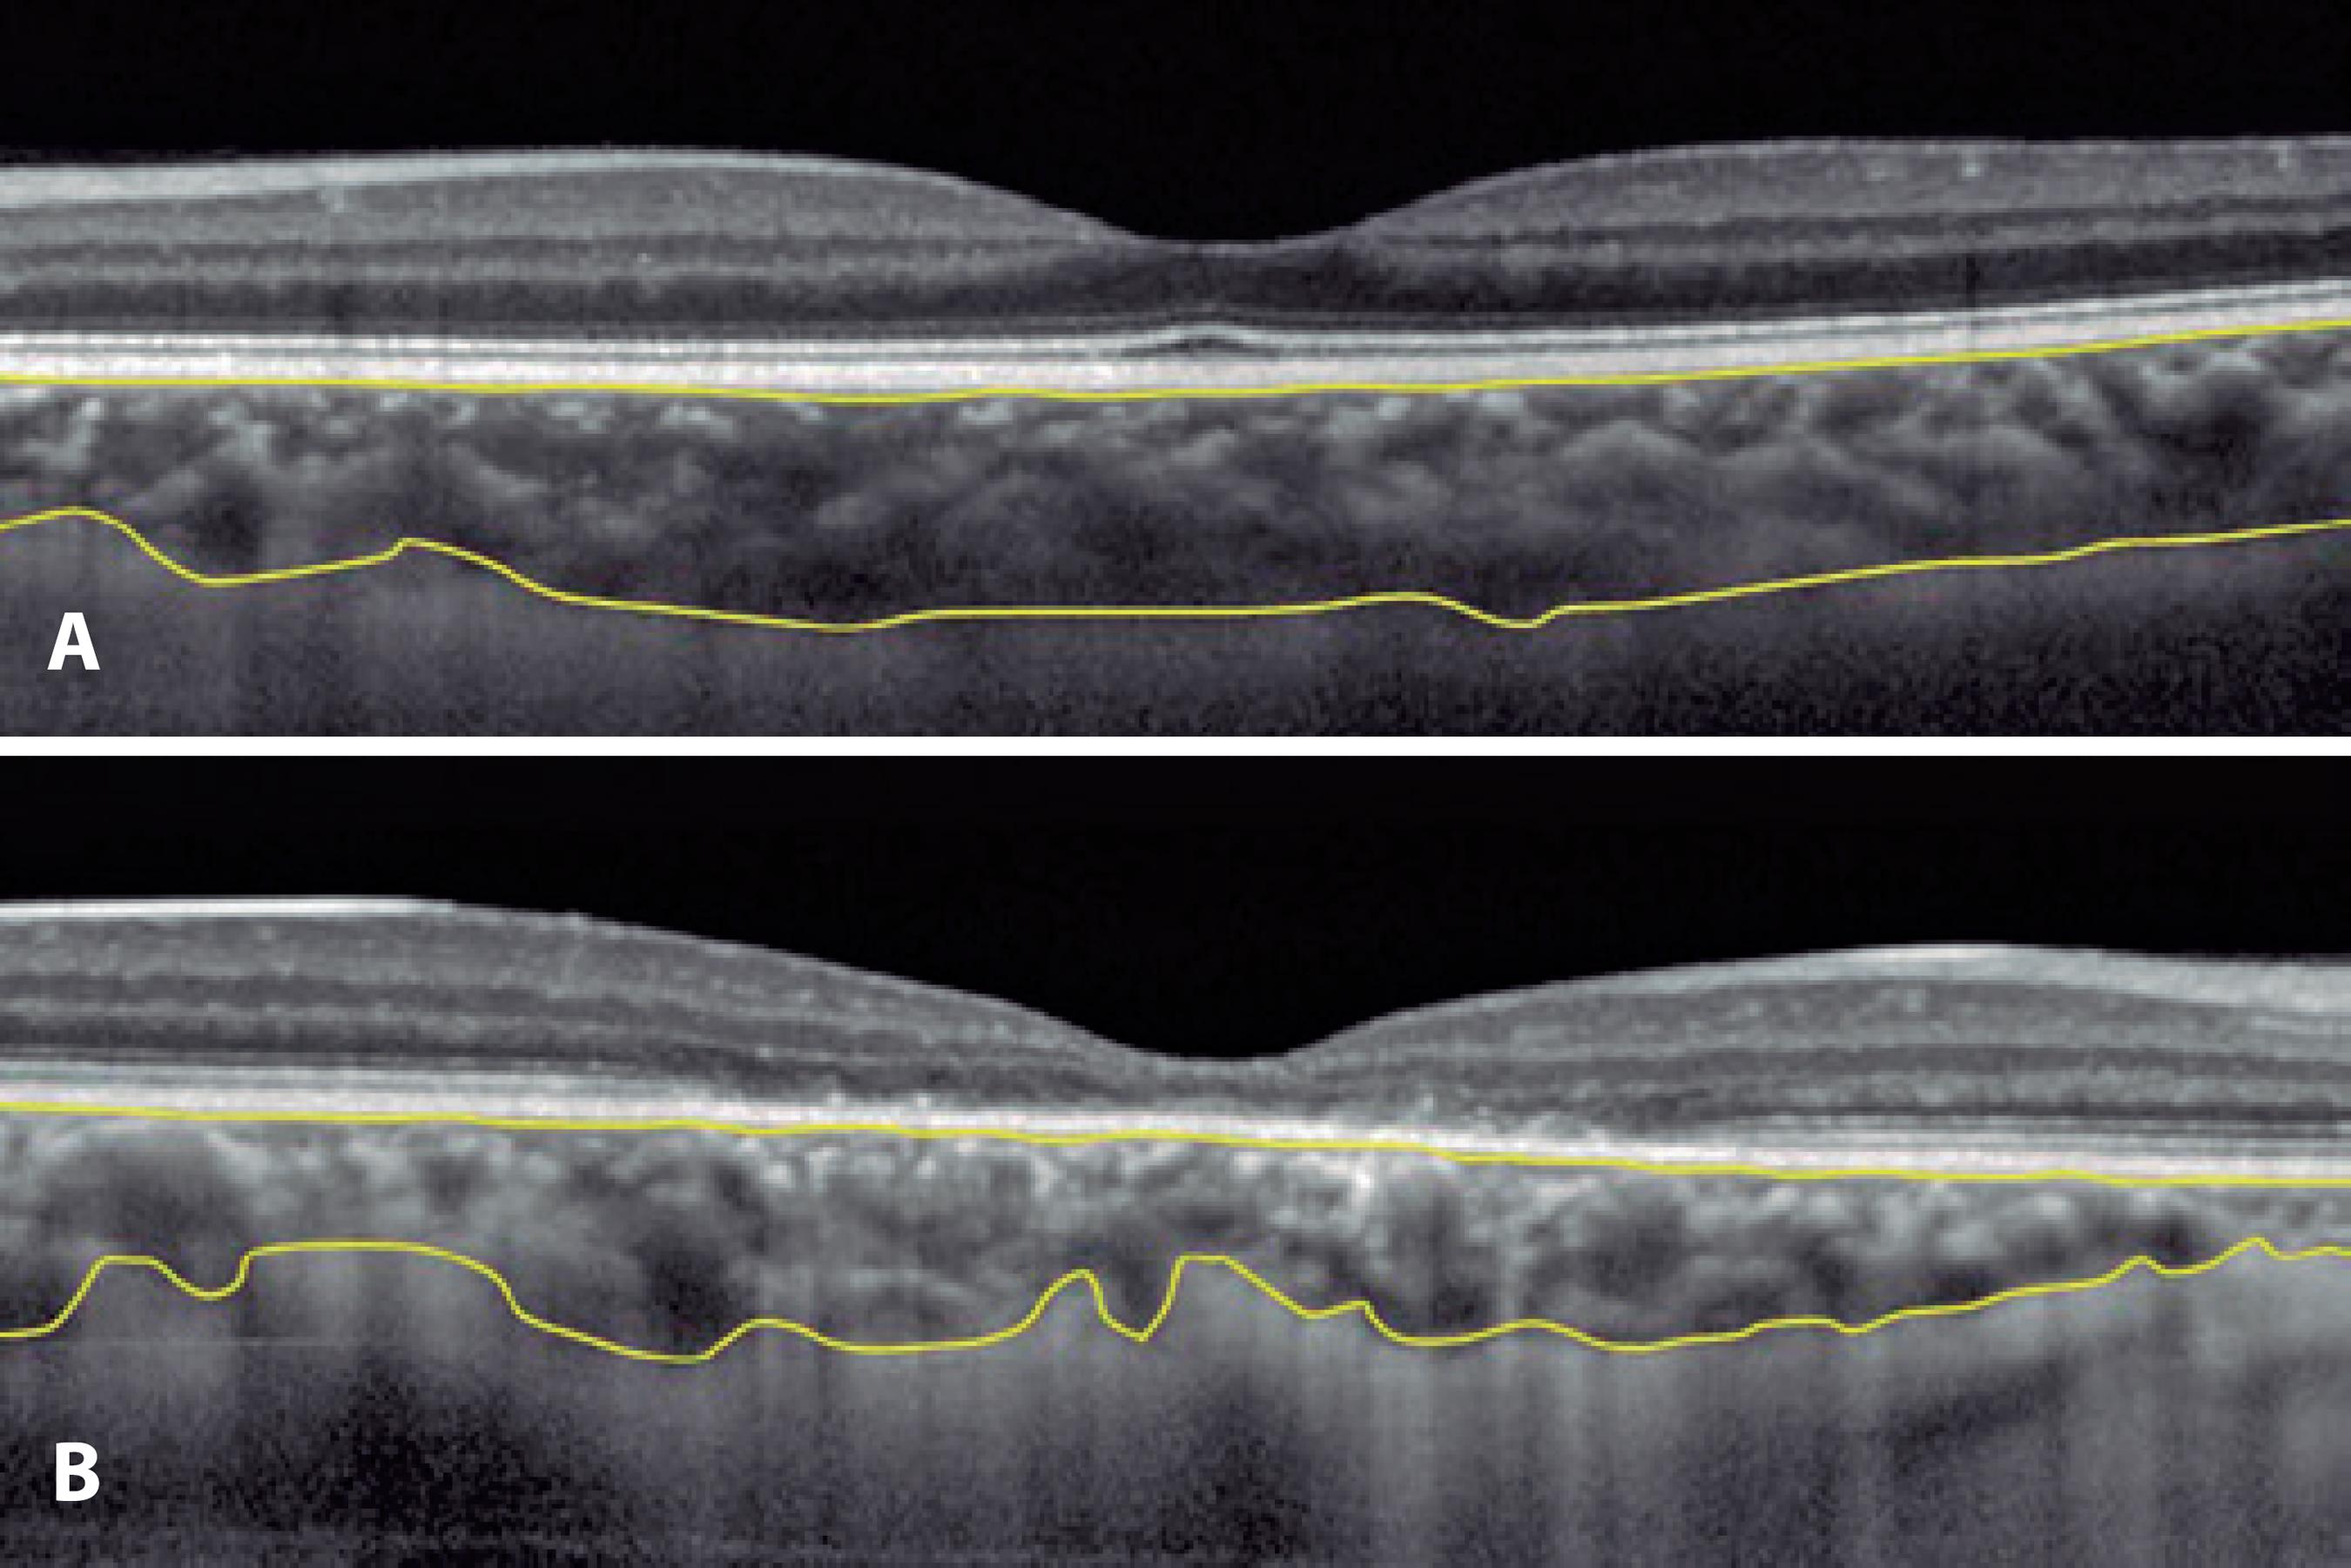

All subjects were examined using EDI-OCT imaging with pupil dilation. All EDI-OCT images were obtained by the same experienced technician in ambient lighting in the afternoon. The OCT device was positioned sufficiently close to the eye to obtain an inverted image. Each section was obtained using automatic eye-tracking software, and 100 averaged images were taken to improve the signal-to-noise ratio. A horizontal image across the fovea was obtained for each subject. The choroidal thickness (CT) measurement was performed manually in a vertical direction from RPE/Bruch's membrane interface to the sclerochoroidal interface (Figure 1). The choroid was independently measured by two blinded observers (OA and GO) at the foveal center and at 500 and 1,500 μm from the nasal and temporal regions to the center of the fovea, respectively. The measurement locations were determined according to the cone cell density in the retina(6).

Figure 1 Measurement of choroidal thickness with enhanced depth imaging optical coherence tomography. The upper yellow line indicates the retinal pigment epithelium/ Bruch's membrane interface, and the lower yellow line indicates the sclerochoroidal interface. (A) Healthy control with a choroid of normal thickness and (B) cone dystrophy patient with choroidal thinning.